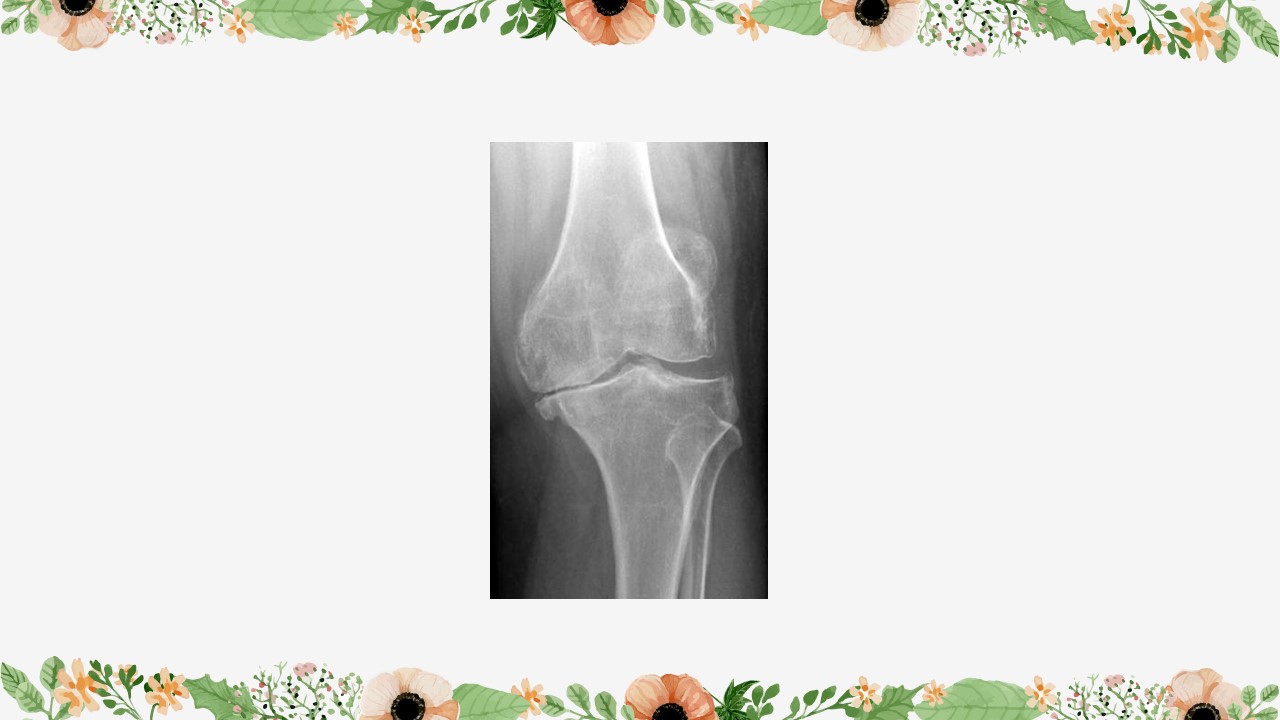

“膝关节骨性关节炎护理查房PPT” 的相关文章